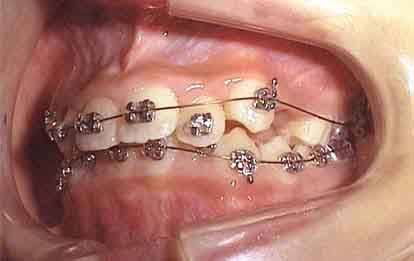

治療開始1年後